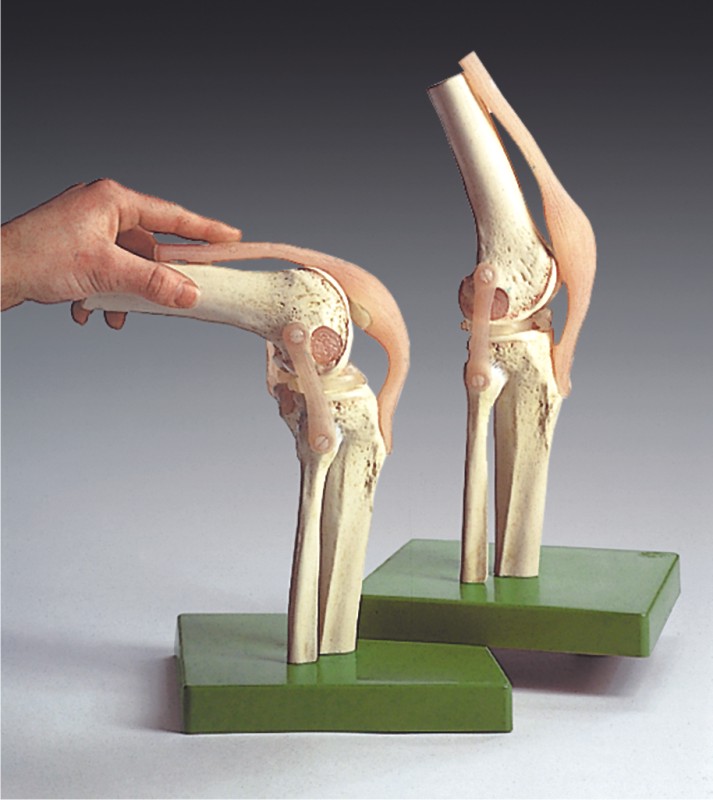

www.fruugo.es3d Anatomically Correct Knee Model

www.fruugo.es3d Anatomically Correct Knee Model

3d Anatomically Correct Knee Model

www.turbosquid.comknee anatomically correct

www.turbosquid.comknee anatomically correct

pikbest.com3d Anatomically Correct Knee Model

pikbest.com3d Anatomically Correct Knee Model

Dynamic Knee Model - Modeling Anatomical Accuracy

dynamicdiscdesigns.comFlüssigkeit Im Knie – Heilpraxis

dynamicdiscdesigns.comFlüssigkeit Im Knie – Heilpraxis

Functional Model Of The Knee Joint - MedWest Medical Supplies

www.medwest.caknee model joint functional anatomical models medwest medical educational products ca ns50

www.medwest.caknee model joint functional anatomical models medwest medical educational products ca ns50